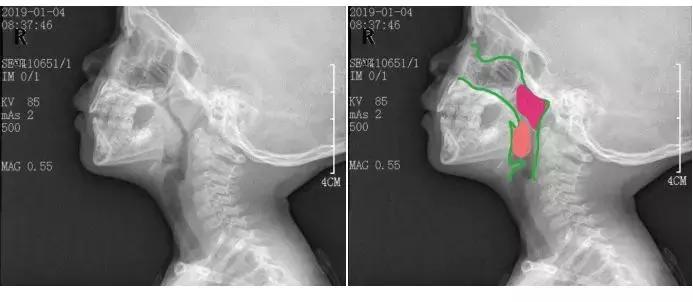

大家一起看一下这两张图片,“口呼吸”是如何让我们变丑的。

(图片来源于呼噜医生 卢晓峰教授)

绿色的是正常上呼吸道,红色是肥大的腺样体,橙色是肿大的扁桃体。这是扁桃体和腺样体都严重肥大的X线片,严重堵塞气道,成一细缝了。这样儿童就会不得不张口呼吸或者前伸脖子前扯下颌呼吸,演变出龅牙,小下颌,长脸,地包天等面容。